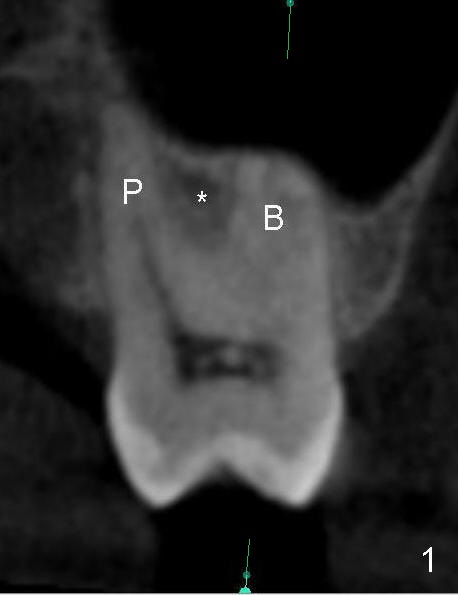

The upper 2nd molar have 3 roots with limited furcation. The buccal ones may be fused (Fig.1 (CT coronal section),2 (sagittal)). After extraction, there are 2 sockets (Fig.1'). When 3 roots are fused, there is a single large socket.

When the buccal roots are fused, there are 3 potential sites for immediate implant (Fig.1'): septum (*), buccal (B) and palatal (P) sockets. Septal placement (6.9x8 mm bone level implant) is the most ideal for restoration (Fig.3). The length of the implant can be increased (10 mm) with sinus lift so that the base of the implant between the buccal and palatal apices in height (Fig.4). Primary stability is derived mainly from the implant body engagement into the septum (Fig.5 coronal section through the septum). If bone density in the septum is high, a small implant may be appropriate (Fig.6,7: 6.4x8 mm). The large implant (6.9 mm) is chosen so that amount of bone graft to be used (Fig.8 red circles) is less.